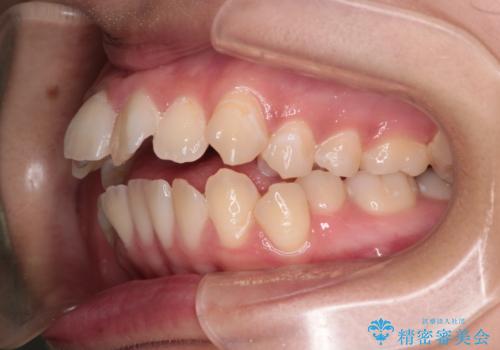

【インビザライン】シザーズバイト、抜歯矯正

- オープンバイトを主訴に来院された患者様です。

抜歯を行うことで、インビザラインを用いて前歯を下げることができ、同時にオープンバイトを改善することができました。

今回はインビザラインのみで治療を終了することができました。